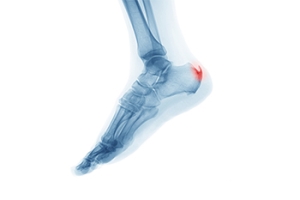

Do I Have Heel Spurs?

Many people have heel spurs and don’t even know it. Heel spurs are actually calcium deposits in the heel of the foot, and can grow up to half-an-inch long. Most often they cause a dull ache or tenderness, and sometimes a sharp pain in the morning when you first stand up. Extreme heel pain is more often caused by plantar fasciitis, but the two conditions are often linked. The most common causes of heel spurs are running on hard surfaces, obesity, and wearing non-supportive footwear, such as flip-flops. If you frequently experience severe heel pain, please see a podiatrist for diagnosis and treatment.

Heel spurs are formed by calcium deposits on the back of the foot where the heel is. This can also be caused by small fragments of bone breaking off one section of the foot, attaching onto the back of the foot. Heel spurs can also be bone growth on the back of the foot and may grow in the direction of the arch of the foot.

Older individuals usually suffer from heel spurs and pain sometimes intensifies with age. One of the main condition's spurs are related to is plantar fasciitis.

Pain

The pain associated with spurs is often because of weight placed on the feet. When someone is walking, their entire weight is concentrated on the feet. Bone spurs then have the tendency to affect other bones and tissues around the foot. As the pain continues, the feet will become tender and sensitive over time.

Treatments

There are many ways to treat heel spurs. If one is suffering from heel spurs in conjunction with pain, there are several methods for healing. Medication, surgery, and herbal care are some options.